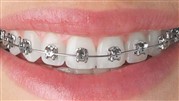

ارتودنسی

یکی از روشهای درمانی و زیبایی در دندانپزشکی ارتودنسی است که با استفاده از آن میتوان دندانهای به هم نزدیک و یا از هم دور را در یک ردیف منظم قرار داد. ارتودنسی شامل سیمها و براکت است و با گذر زمان فواصل دندانی را منظم میکند.